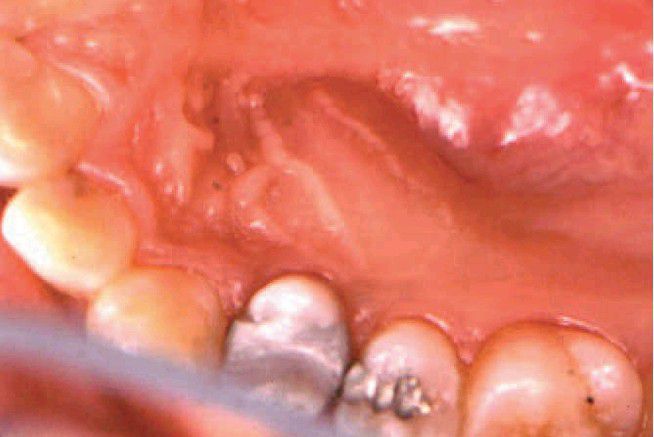

Palatal space infection

Fluctuant swelling in the anterior palate associated with periradicular disease from the lingual root of the maxillary first premolar.